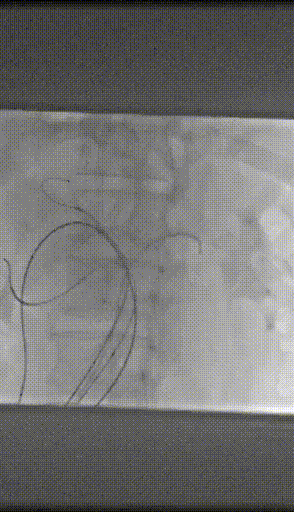

I期腔内修复过程:

肾动脉至肠上区无破口,病情进展后又进行了二期干预

胸腹主动脉瘤四开窗内脏区重建+远端髂总大破口栓塞

术后效果良好,各分支通畅